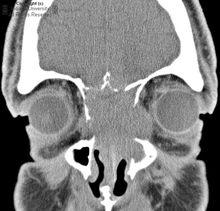

概述? 病理學?未分化癌,醫學病理名稱,發病率僅次於鱗癌,多見於男性,發病年齡較輕。一般起源於較大支氣管,居中央型肺癌

概述 臨床表現 病理改變 治療小細胞未分化癌(簡稱小細胞癌) 是肺癌中惡性程度最高的一種,約占原發性肺癌的1/5。患者年齡較輕,多在40-50歲左右,多有吸菸史。多發於肺門附近的大支...

百科名片 簡介 小細胞肺癌的手術療法 小細胞肺癌的放療 小細胞肺癌的化療melan 3.鼻腔鼻竇黑素瘤Sin melan